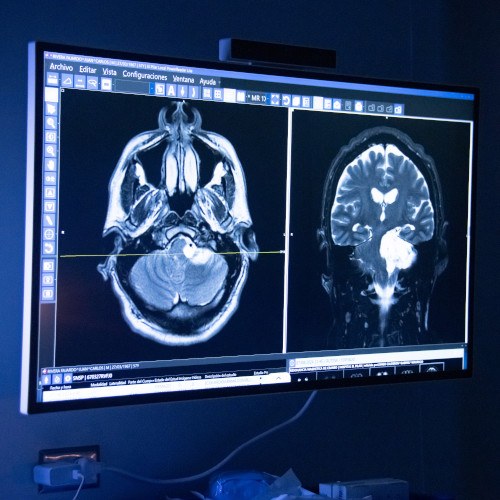

Descripción de la foto para personas con discapacidad visual: equipo neuronavegador en una clínica limpia, amplia y moderna. (Crédito: Hospital El Pilar)

Este centro de atención especializado es un área en el hospital destinada al tratamiento de pacientes con enfermedades neurovasculares. Cuenta con un equipo multidisciplinario y entrenado en la patología, conformado por neurólogos, neurointervencionistas, neurocirujanos, radiólogos y cardiólogos.